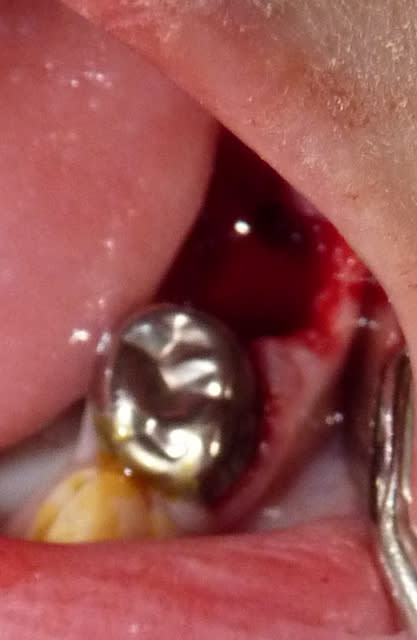

27/07/11 : secteur III.

75 : polype pulpaire. Dent conservable mais nécessitant une pulpectomie dans un contexte difficile. Dent stratégiquement importante pour empêcher la mésialisation de 36.

Décision d'avulser, peut être à tort.

74 : Pulpo, moignon CVI, CPP.

Fluoration.

31 nfo54k - Eugenol

32 aiykgg - Eugenol

33 lrmdgs - Eugenol

34 fqrbmu - Eugenol